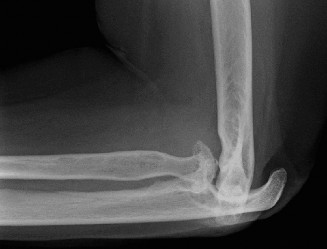

It should be noted that reverse total shoulder arthroplasty is also the procedure of choice in patients with cuff-tear arthropathy (aka rotator cuff arthropathy). Characteristics of cuff-tear arthropathy include superior migration of the humerus due to a massive rotator cuff tear, glenohumeral joint destruction, subchondral osteoporosis, and humeral head collapse (see Fig. 2–17). A reverse total shoulder

Figure 2–17_X-rays of a patient showing evidence of cuff tear arthropathy. The humerus is migrated superiorly, the glenohumeral joint is destroyed, there is subchondral osteoporosis, and the humeral head is collapsed. (From Ecklund KJ, Lee TQ, Tibone J, Gupta R. Rotator cuff tear arthropathy. _J Am Acad Orthop Surg. 2007;15(6):340–349.)